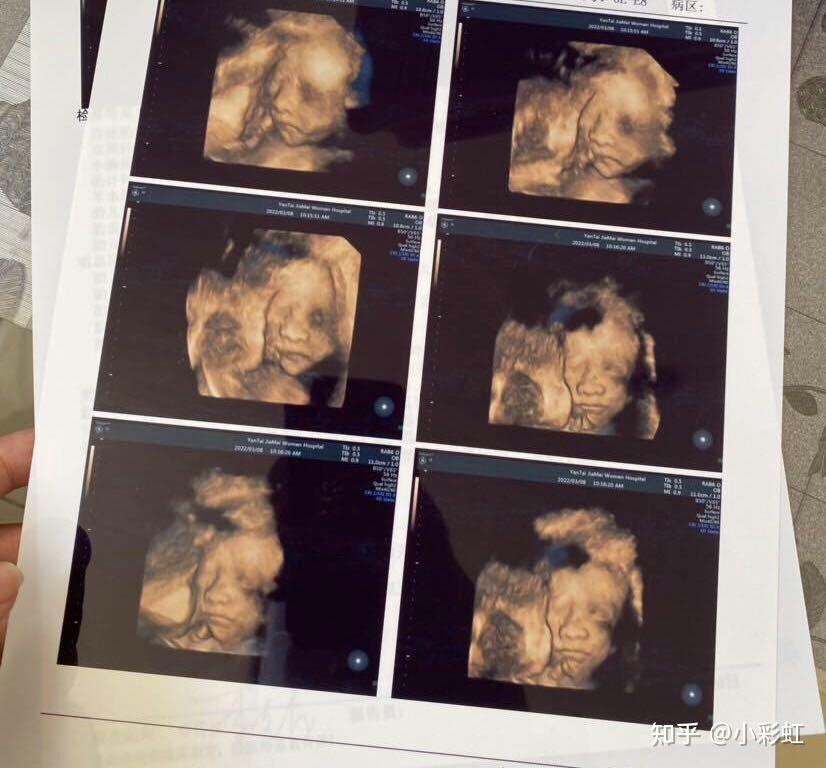

宝宝四维的照片!之后的一切都比较顺利,出胎心,NT顺利通过,虽然备孕路还是挺辛苦的,但是幸好还是试管一次成功了。所以我还是觉得自己是幸运的。也很谢谢陪我一路走过的家人,朋友,还有我老公时刻的关心,我才有力量和勇气完成试管这一系列流程。祝愿姐妹们都能早日好孕,顺顺利利得和自己的宝贝见面。